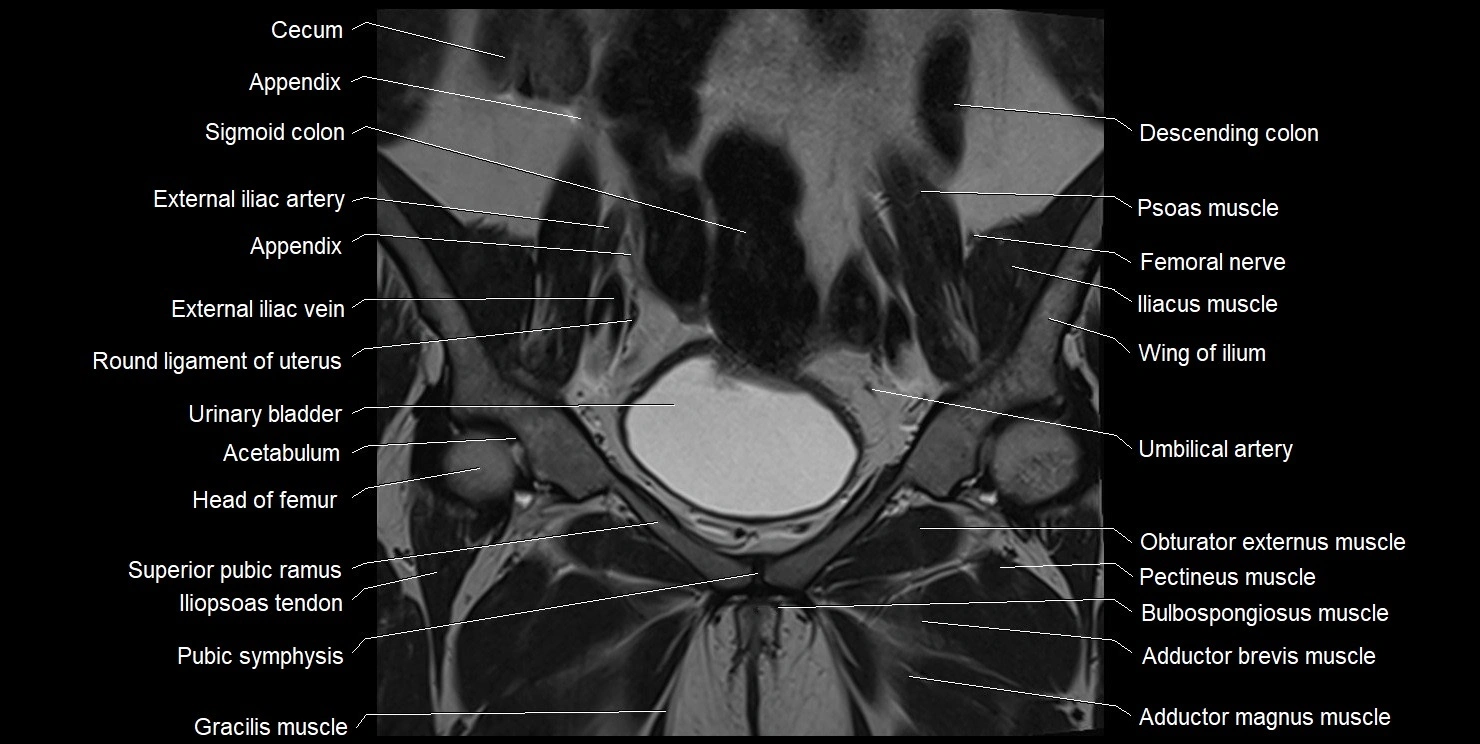

- Acetabulum

- Adductor brevis muscle

- Adductor longus muscle

- Adductor magnus muscle

- Body of pubis

- Body of urinary bladder

- Bulbospongiosus muscle (Female)

- Cecum

- Clitoris

- External iliac artery

- External iliac vein

- Femoral nerve

- Gracilis muscle

- Head of femur

- Ileum

- Iliopsoas muscle

- Iliopsoas tendon

- Iliopubic eminence

- Pectineus muscle

- Obturator externus muscle

- Pubic symphysis

- Pubic tubercle

- Round ligament of uterus

- Superior pubic ramus

- Umbilical artery

- Urinary bladder